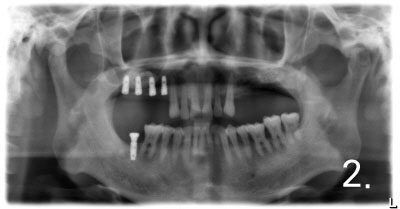

Maxillary Sinus Bone Graft

Case #1

There is not enough bone to place implant on upper and left side.

Performed sinus graft more than 90% of bone required to place implant

Placing implant in bone graft site

Implant crown was fabricated